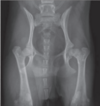

Avascular necrosis of femoral head - Young dogs - Small and toy breeds legg-calve-perthes disease

Feline capital metaphyseal osteopathy sorta like the cat version of -legg-perthes' Young male neutered cats mostly. Extensive lysis and bone remodeling of the neck. Secondary fractures